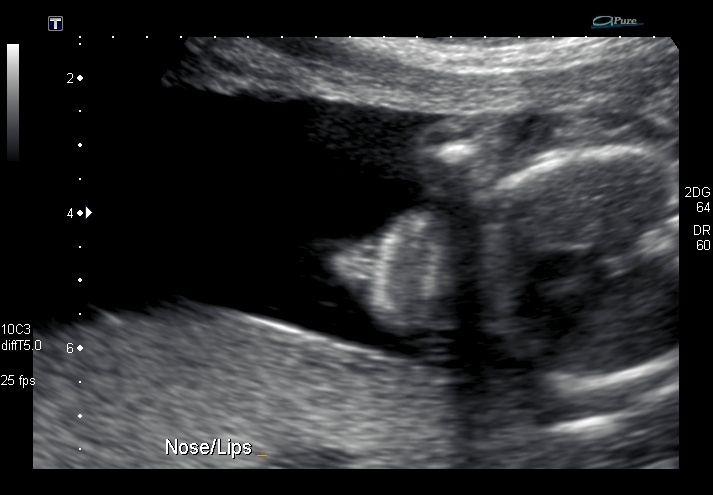

Hi there, I *think* this is a potty shot, what are your predictions and how sure are you? Thanks!!

EDITED TO ADD: I didn't want to know the sex at the time so it's quite possible I don't have any shots that will show the gender. But this one is looking up towards the chin, up at the nose. And on the right, looks to me like a potty shot, two legs with something in between!